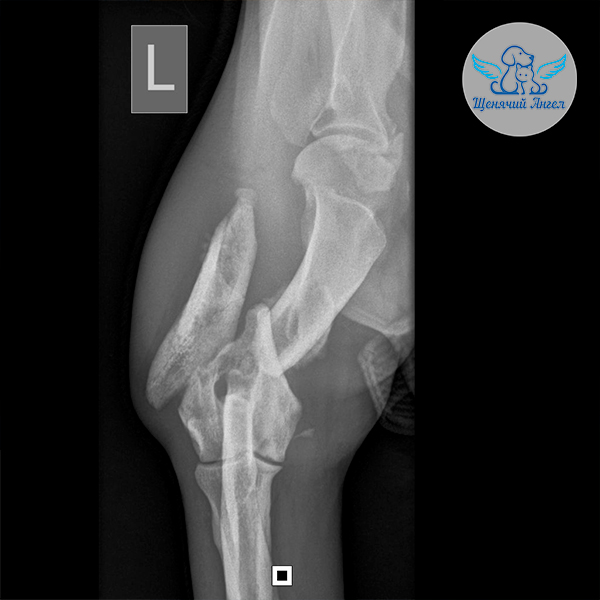

Когда состояние стабилизировалось, мы перевезли Аллочку в Москву на консультацию к хирургу Илье Фёдоровичу Вилковыскому 👨🏻‍⚕️(Ветеринарный центр «МЕДВЕТ»). Рентген выявил комплекс повреждений опорно-двигательного аппарата. На левую переднюю лапу она не может опираться из-за перелома плечевой кости и отрыва надсуставного бугорка лопатки 🥺. Задние лапки также пострадали: справа – вывих тазобедренного сустава, слева – переломы подвздошной, тазовой и лонной костей 😢.

– Левая передняя лапа: необходимо собрать и стабилизировать плечевую кость, чтобы обеспечить правильное сращение.